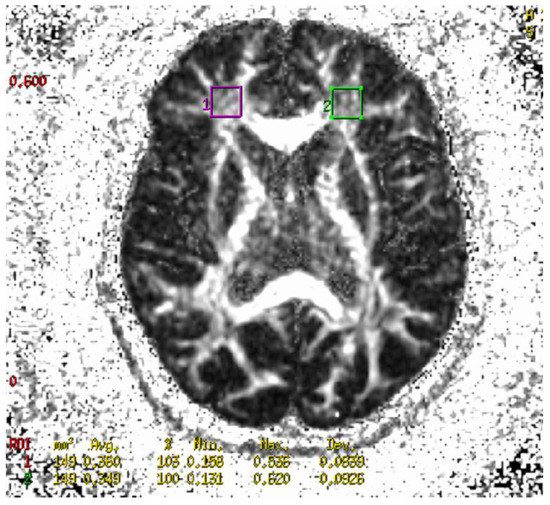

4.6. Neuroimaging Analysis